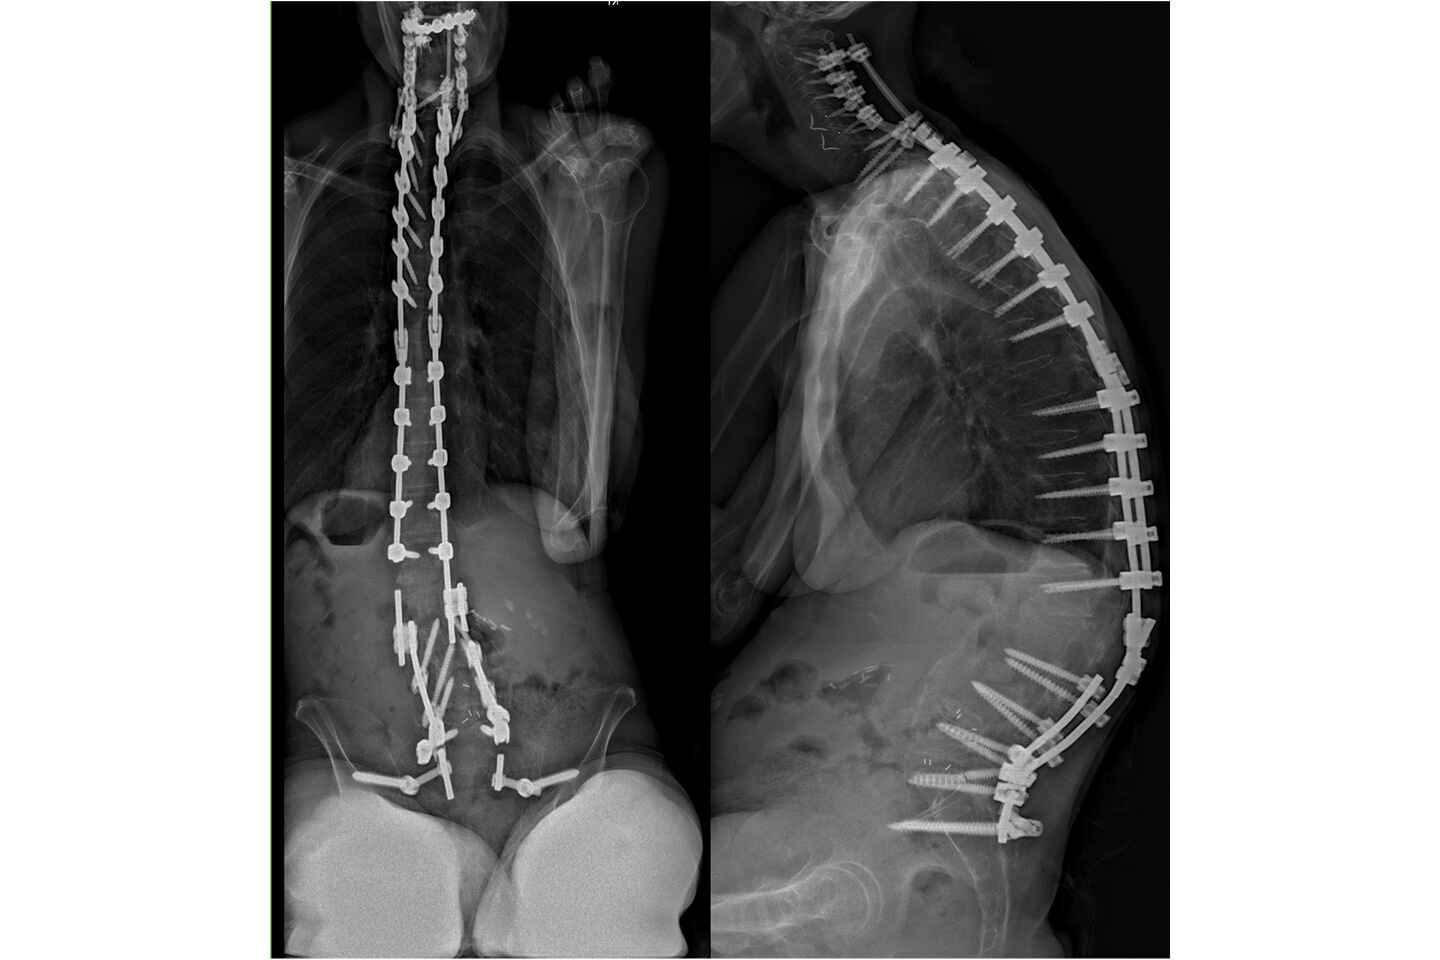

• Imaging revealed a prior instrumented fusion from C2 to the pelvis with multiple rod fractures, pseudoarthrosis, and severe spinal deformity (kyphoscoliosis).

X-ray imaging revealed multiple prior fusions connected together from C2 to the pelvis. The rods were clearly fractured in multiple places. The combination of rod fracture and failure, together with pseudoarthrosis, had led to a severe and progressive spinal deformity. Extensive nonoperative treatments had failed to bring relief and multiple surgeons and intuitions had told her there were no other options.

Preoperative X-rays showing multiple prior fusions spanning C2 to the pelvis, with rods clearly fractured in several locations. Source: NYU Langone Health